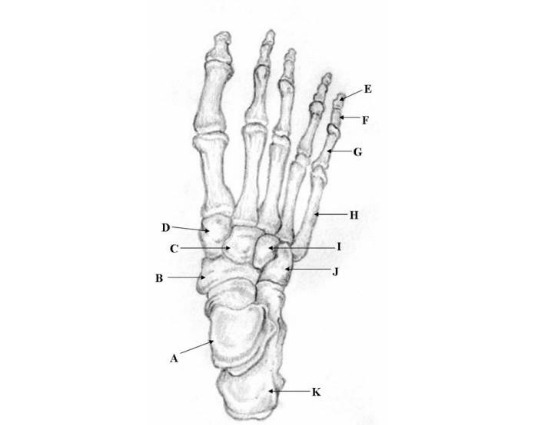

Two unlabeled illustrated images, figures 1 and 2, of the foot and one unlabeled x-ray image, figure 3, were selected. Each image was inputted into ChatGPT Version 4o and the model was prompted to identify the bones depicted in each image using the following prompt.

Prompt 2: ‘Identify the structures labeled in this image’

Two prompts were entered into ChatGPT (Prompt 1: “Make me a picture of human foot with the bones labeled”, Prompt 2: “Identify the structures labeled in this image”). Results of prompt 1, seen in figure 4, are that the generated image was detailed and visually appealing, correctly displaying a foot with visible bones as requested. However, the labeling is entirely inaccurate, with misspelled anatomical terms, misplaced labels, and several missing bones, including the phalanges of the 4th toe. The result of prompt 2 for the first illustrated image is 27% accurate with 3 of 11 bones accurately identified as shown in table 1. The result of prompt 2 for the second illustrated image is 57% accurate with 4 of 7 bones accurately identified as shown in table 2. The result of prompt 2 for the x-ray image is 0% accurate with 0 of 19 structures accurately identified as shown in table 3.

Out of 11 labels, 3 were identified correctly, resulting in an accuracy of 27%.

The output from ChatGPT v4o of prompt 1 "‘Make me a picture of human foot with the bones labeled’ demonstrates a visually appealing and detailed depiction of a human foot with visible bones. However, the labeling is inaccurate, with anatomical terms misspelled, labels misplaced, and several key bones, such as the phalanges of the 4th toe, completely missing. Prompt 2 reveals varying accuracy between the 3 images used: 27% for the first illustrated image, 57% for the second illustrated image, and 0% accuracy for the x-ray image.